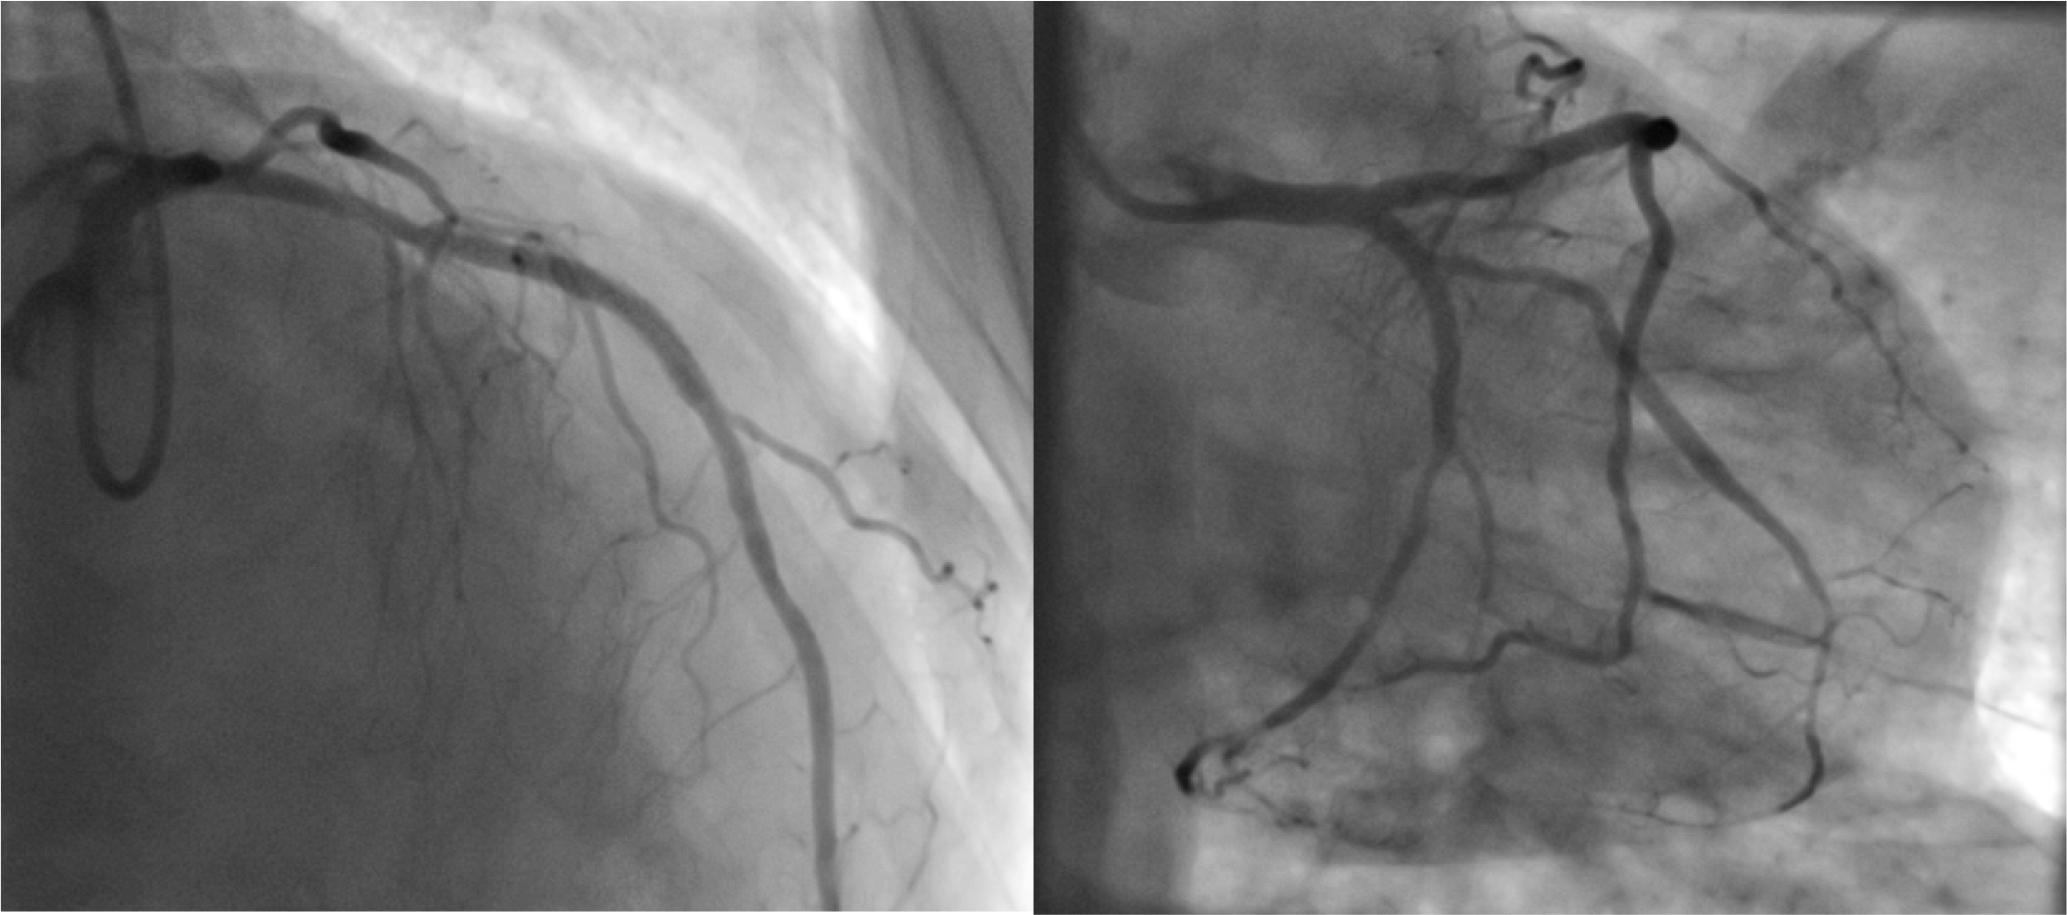

Figure 3